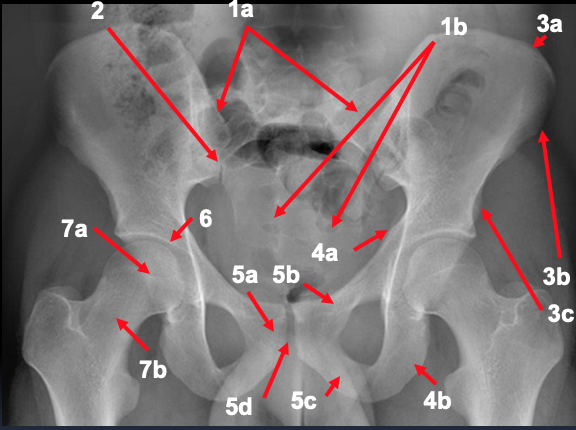

What is represented by 1 and 2 in the AP pelvic radiograph?

1. sacrum

a. ala

b. foraminae

2. sacroiliac joint

What is represented by 3 and 4 in the AP pelvic radiograph?

3. ilium

a. crest

b. ASIS

c. AIIS

4. ischium

a. spine

b. tuberosity

What is represented by 5 in the AP pelvic radiograph?

5. pubis

a. body

b. superior ramus

c. inferior ramus

d. symphysis